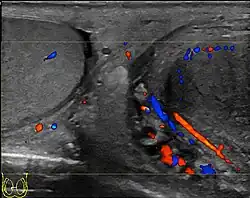

- Ultrasound scanning

Ischemic orchitis may result from damage to the blood vessels of the spermatic cord during inguinal herniorrhaphy, and may in the worst event lead to testicular atrophy.[3]

- Lefort C, Thoumas D, Badachi Y, et al. (July 2001). "Orchites ischémiques: À propos de 5 cas diagnostiqués en écho-Doppler couleur" [Ischemic orchiditis: review of 5 cases diagnosed by color Doppler ultrasonography]. Journal de Radiologie (in French). 82 (7): 839–42. PMID 11507447. INIST 1080037.